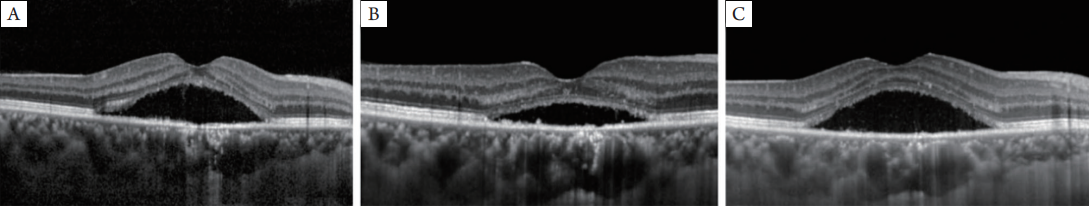

图7 OCT图片显示PDT术后1个月(A)、3个月(B)和6个月(C)随访中黄斑区持续的SRF

图8 OCT图片显示SMLP术后1个月(A)、3个月(B)和6个月(C)随访中的黄斑区,图像表明SRF在术后3个月和6个月完全吸收